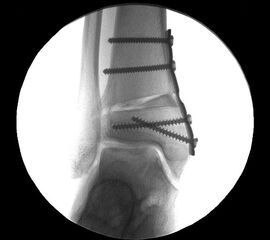

Abbildung 17

Gleichzeitig bestehende Achsdeformitäten oder Instabilitäten sind im Rahmen des Eingriffs ebenfalls zu therapieren. Hierbei können alle Verfahren der Rückfusskorrektur eingesetzt werden. Auch Kapsel-Band-Rekonstruktionen sind nach den Standard-OP Techniken möglich. Abbildung 17 zeigt einen Patienten mit gleichzeitig durchgeführter supramalleolärer Korrekturosteotomie.